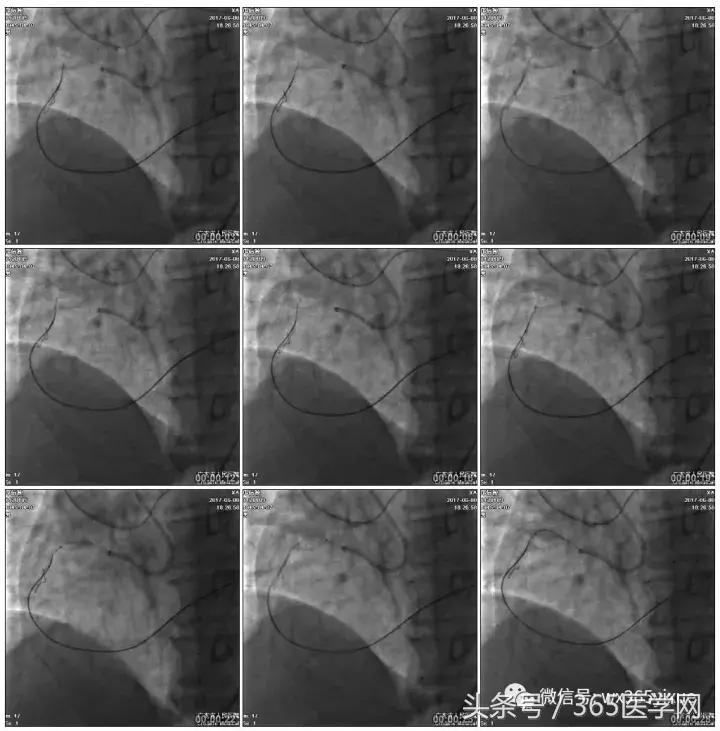

正向浅尝,改为逆向,LCX-PL

RRA:6F AL0.75 GC –RCA;

RFA:7F XB 3.5 GC—LCA 150cmcorsair

正向130cmFinecross微导管支持下尝试送PILOT150、Gaia 2导丝无法通过RCA闭塞段

SION导丝通过侧枝

逆向导丝:更换Gaia2

正向导丝:Gaia2,PILT150

正向导丝knuckle